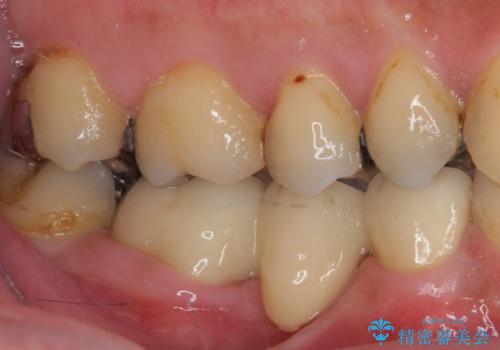

残念ながら抜歯が必要となりましたが、しっかりと診断を行ったことで、患者様も抜歯に納得していただけました。

抜歯後は痛みがあっという間に引き、ブリッジ補綴後は安定して咬めるようになりました。